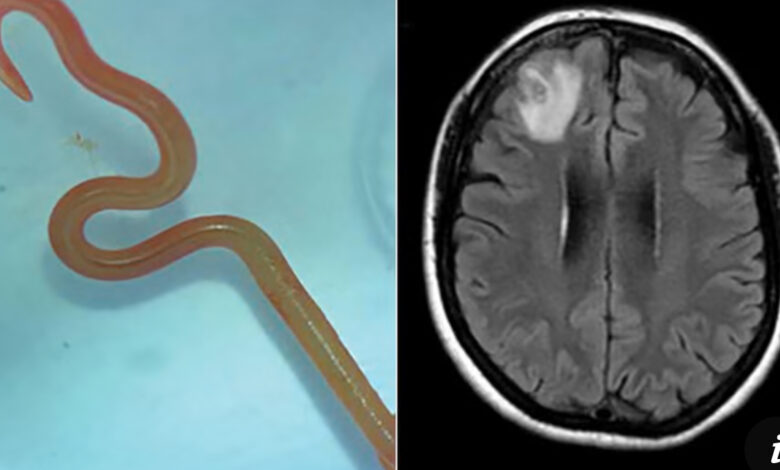

Uma descoberta médica inédita deixou profissionais de saúde do mundo inteiro surpresos. Uma mulher de 64 anos foi submetida a exames após meses de dores de cabeça, lapsos de memória e cansaço extremo. O que parecia ser apenas um problema neurológico comum se revelou um caso jamais registrado em humanos. Médicos encontraram um verme redondo vivo, de aproximadamente 8 centímetros, dentro do cérebro dela.

O caso aconteceu na Austrália e foi descrito em detalhes na revista científica Emerging Infectious Diseases. Segundo os especialistas, o parasita encontrado no cérebro da paciente era da espécie Ophidascaris robertsi, comum em cobras píton e totalmente desconhecido como agente de infecção humana. O parasita estava se movendo entre tecidos cerebrais quando foi localizado em exames de imagem.

A cirurgia para retirada aconteceu imediatamente após a descoberta. A equipe médica relatou que o verme estava vivo e ativo no momento da remoção. O procedimento exigiu extremo cuidado para evitar danos neurológicos permanentes. A paciente se recupera bem e continua sob acompanhamento para tratar possíveis infecções secundárias causadas pelo parasita.